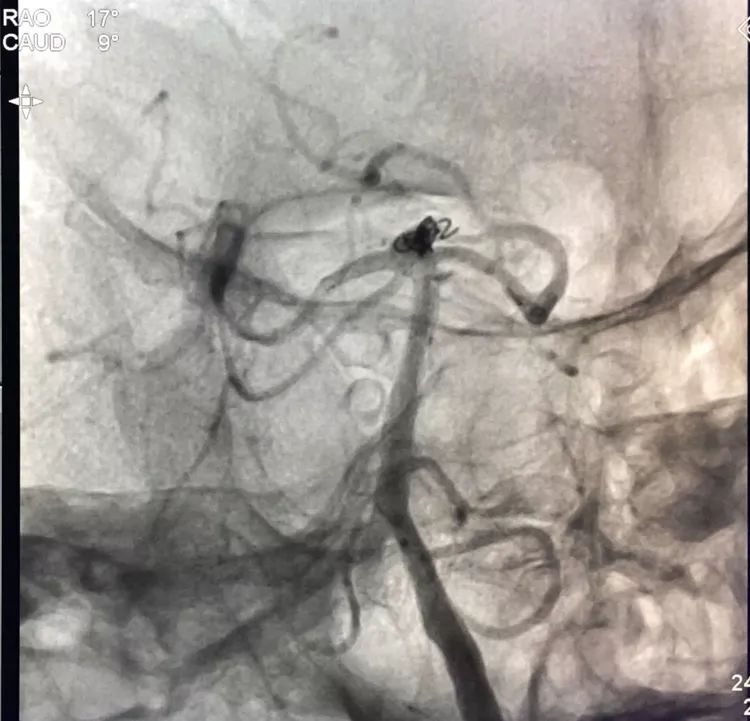

微导管头顶在支架网眼处,投送一枚1.5-2的小圈,一开始弹簧圈走行入载瘤动脉(支架)内,用扭具调整弹簧圈头端的行进方向,并随之微调微导管头的方向和张力,圈终于成功钻入死腔!

再投入一枚1.5-3的小圈

继续钻入一枚1.5-2的小圈

嗯,完美收官!

回到工作位造影,显示基底动脉顶端动脉瘤完全栓塞,基底动脉顶端四根血管畅通。